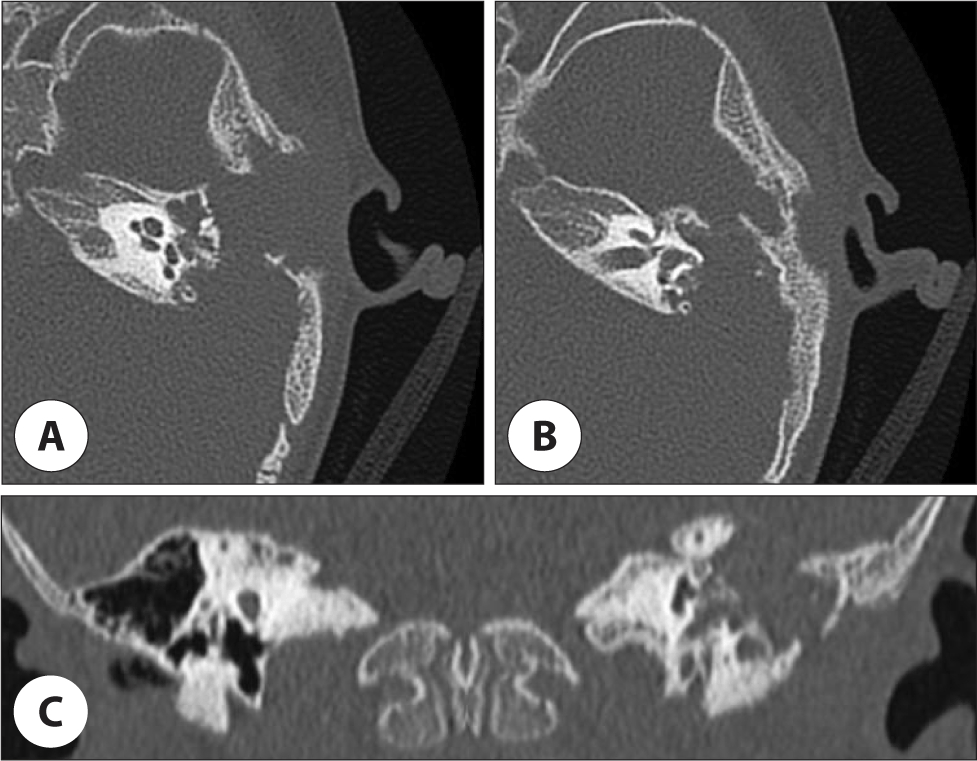

그러나 2개월 후 외이도 후방에서 종물이 돌출되는 양상으로 외이도 협착이 관찰되었고(Fig. 1B), 청성뇌간유발반응검사상 우측 30 dBnHL, 좌측 70 dBnHL로 좌측 난청 소견을 보였다. 정밀한 검사를 위해 측두골 전산화단층촬영(computed tomography, CT)을 시행하였다. CT에서는 좌측 유양돌기(mastoid), 측두골 인부(squamous part), 측두하악관절(temporomandibular Joint, TMJ)의 전방 및 상부, 외측 반고리관(lateral semicircular canal) 누공을 포함하는 광범위한 골 파괴성 병변이 확인되었으며, 중이강(middle ear cavity)에도 병변 침범이 확인되었으나 이소골의 파괴 소견은 명확하지 않았다(Fig. 2). 이후 확산 강조 자기공명영상(diffusion-weighted MRI[magnetic resonance imaging])에서는 동일 부위에 확산 제한 소견(diffusion restriction)을 동반한 병변이 관찰되어 진주종을 의심하였다(Fig. 3).